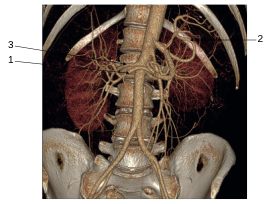

Fig. 35.6 Angioscanner de l’aorte avec reconstructions 3D en vue de face.

1. Artère hépatique commune. 2. Artère splénique. 3. Artère rénale droite.

Source : CERF, CNEBMN, 2022.